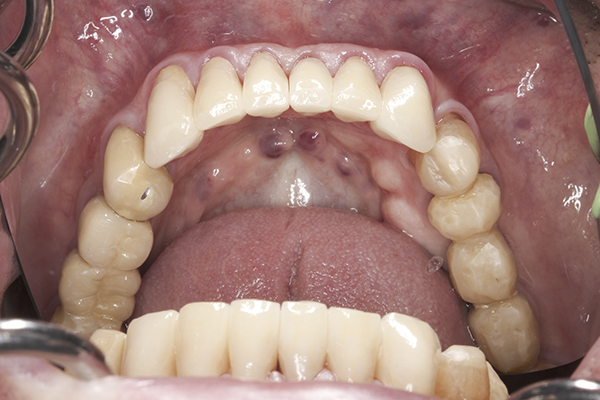

(15.) Preoperative maxillary, occlusal view.

Figure 15